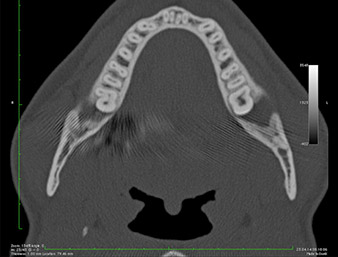

Nell'immagine 3D (tomografia volumetrica digitale) era visibile che il residuo di radice era collocato in posizione distocaudale nella transizione dalla porzione orizzontale alla porzione ascendente della mandibola (Fig. 2).